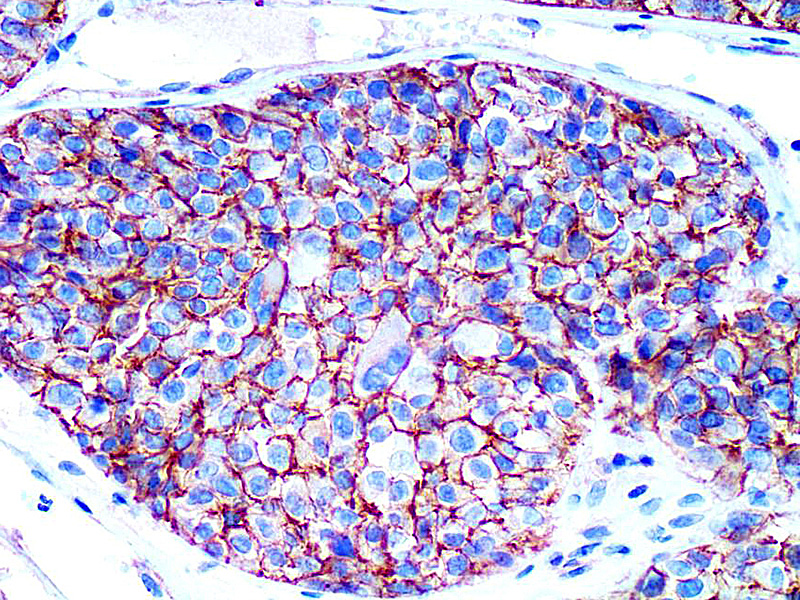

图片:

KBA.62 (Melanoma Associated Antigen) Antibody (P1009) on Melanoma